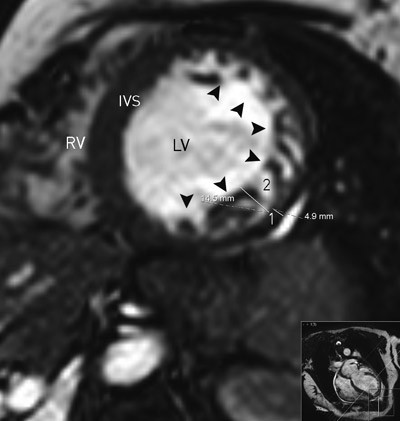

Increased knowledge about the pathogenesis, diagnostic characteristics and prognosis of LVNC has recently caused the condition to be classified as primary cardiomyopathy (17). Echocardiography or MRI of the heart (12) are considered to be diagnostic gold standards.

There is no international consensus about strict diagnostic criteria for LVNC and one or more of the echocardiographic criteria listed above may also be found in other conditions or diseases that affect the LV. However, presence of all the above-mentioned criteria is reported to be highly specific for LVNC (11). When findings are equivocal, intravenous echocardiographic contrast agents may help to make the diagnosis (18). In magnetic resonance images of the heart, a noncompacted/compacted layer ratio ≥ 2.3 (measured in the ventricle’s end diastole) is considered typical for LVNC (12) (fig 3). Other cardiac imaging modalities such as computer tomography and ventriculography may also be useful (19).